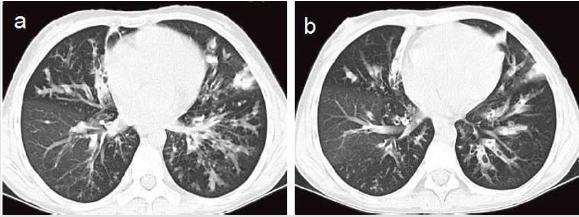

A 15-year-old female presented to our out-patient room with complaints of menstrual chronic cough, sputum production and diffuse bronchiectasis since early childhood (Figure 1). She had a history of T1DM for 3 years and underwent a long-term insulin replacement therapy. Family history suggested that her parents and her little brother were all healthy. The patient was admitted to our hospital for further treatment. Physical examination showed her mild fever of 37.8°C, relative low oxygen saturation of 95% and rough moist rales in bilateral posterior lung fields. Red rashes with clear border and scurf scattered on her head, face and hands, as well as white spots on her oral mucosa (Figure 2). Laboratory tests on admission revealed a white cell count of 15,500/mm3 in which neutrophil dominated (12,540/mm3). Other plasmatic indicators including hemoglobin, platelet, c-reactive protein (CRP), erythrocyte sedimentation rate (ESR), fasting plasma glucose and 2h postprandial glucose level was 122 g/l, 120,000/mm 3,43mg/l, 11mm/h, 23.73 mmol/l and 28.53 mmol/l respectively. Candida albicans grew in the sample of her pharyngeal swab, skin scraper and sputum cultures. We didn’t find positive results in glutamic acid decarboxylase antibody (GADA), insulin autoantibody (IAA), islet cell antibody (ICA), HLA-B27 antigen, rheumatoid factor and antinuclear antibodies (ANA)in the subsequent test. But several results actually took our interest in the immunologic test and genetic analysis. In the immunologic test, the IgA level decreased to 0.07 g/l (normal range 0.8-2.3 g/l) in her plasmatic sample while IgG, IgE, IgM, C3, C4 level were normal. The CD19+cells proportion also decreased to 0.5% (normal range 5-18%) in lymphocyte subgroup analysis. In the genetic analysis, we detected nucleotide change c.1957G>A and amino acid change p.V6531, locating in chr2-191841668 in exon 22. But her parents and brother showed negative results in it (Figure 3), which implied her spontaneous mutation.

The patient was diagnosed with chronic mucocutaneous candidiasis accordingly after dermatologist consultation. We diagnosed bronchiectasis on the basis of HRCT results (Figure 1). We started on antibiotics including piperacillin-tazobactam and oral itraconazole in the setting of secondary infection of bronchiectasis as well as continue the insulin replacement therapy for T1DM. After two weeks’ treatment, the symptoms improved significantly.